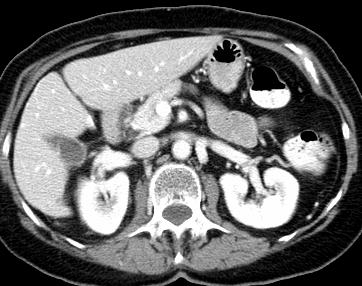

Due to the constraints of the imaging device and high cost in operation time, computer tomography (CT) scans are usually acquired with low intra-slice resolution. Improving the intra-slice resolution is beneficial to the disease diagnosis for both human experts and computer-aided systems. To this end, this paper builds a novel medical slice synthesis to increase the between-slice resolution. Considering that the ground-truth intermediate medical slices are always absent in clinical practice, we introduce the incremental cross-view mutual distillation strategy to accomplish this task in the self-supervised learning manner. Specifically, we model this problem from three different views: slice-wise interpolation from axial view and pixel-wise interpolation from coronal and sagittal views. Under this circumstance, the models learned from different views can distill valuable knowledge to guide the learning processes of each other. We can repeat this process to make the models synthesize intermediate slice data with increasing inter-slice resolution. To demonstrate the effectiveness of the proposed approach, we conduct comprehensive experiments on a large-scale CT dataset. Quantitative and qualitative comparison results show that our method outperforms state-of-the-art algorithms by clear margins.